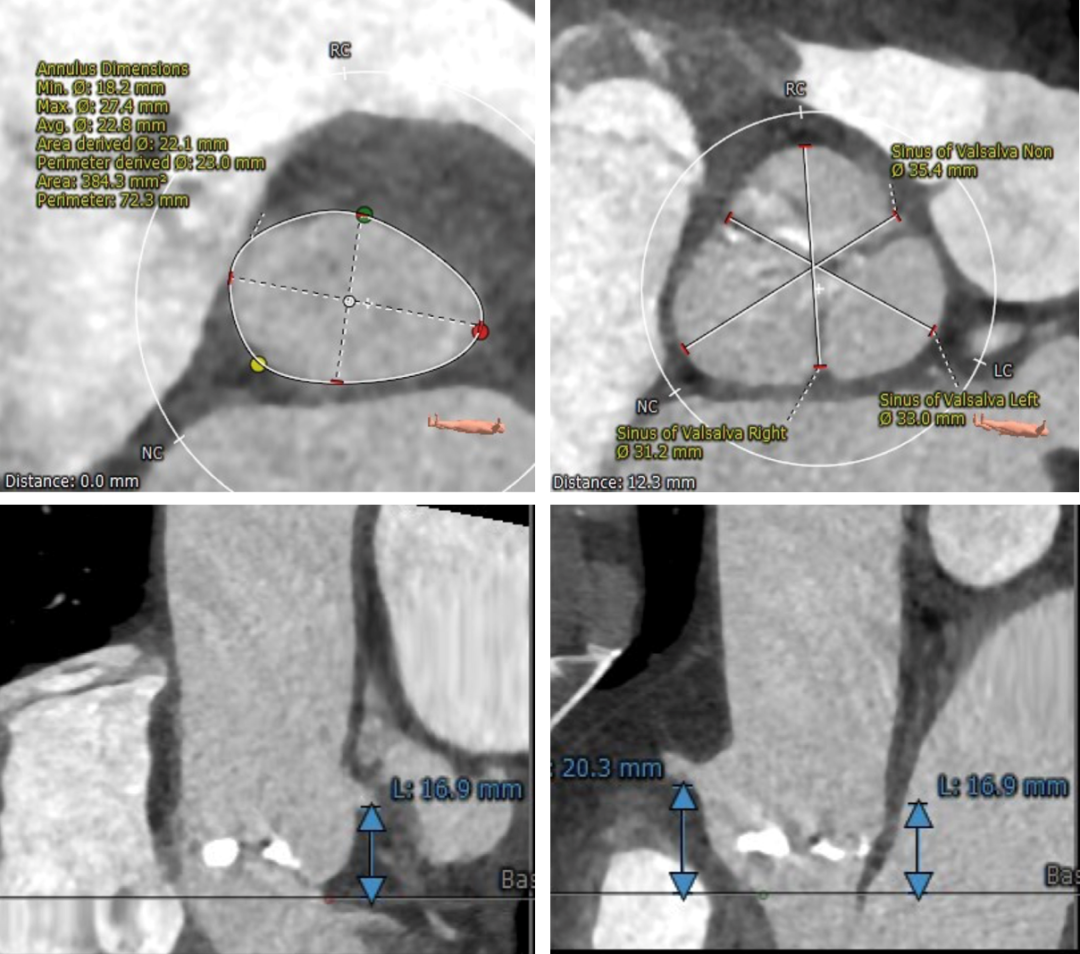

主动脉根部评估:

瓣环平面及瓦式窦平面解剖及冠脉风险评估

左右冠高度可,冠脉存在明显钙化,左冠瓣长度小于冠脉开口与瓣叶附着缘距离,潜在冠脉阻挡风险较低。

瓦氏窦、窦管交界、升主动脉内径可。主动脉瓣环与水平面夹角可,主动脉弓角度与宽度可。